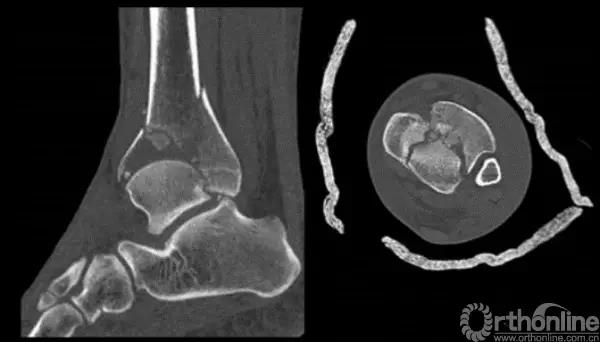

二、 Pilon骨折手术入路选择

他将pilon骨折大致的骨块进行了分类,分别为后、前内、前外三个骨折块。Pilon骨折的入路一共有5个,前内、前正中、前外、后内、后外。

三、Pilon骨折术中技巧

针对该类骨折一般采取小块靠大块的原则,充分显露之后,先从后面开始,逐步把小块往大块上复位,逐渐复位到最前面。

2.中心粉碎骨折

对于中心粉碎骨折需要充分牵引、撑开,将关节面的骨折块先找到摆放在合适的位置,用克氏针将关节面的骨块应用排筏技术先固定好,从下方观察关节面的复位情况,并且确认骨块不会向上推起,适当植骨,然后将骨块前后和左右进行压实后进行固定。